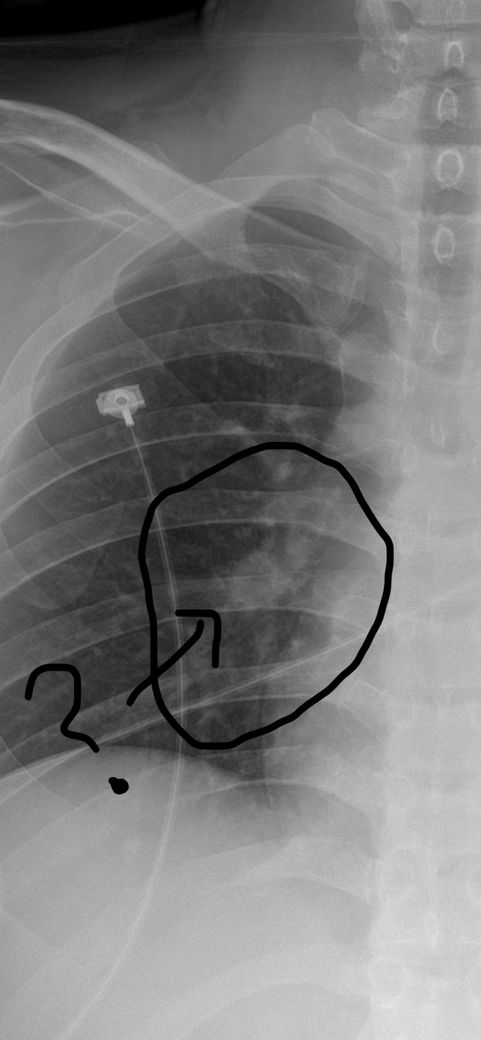

위 사진은 코로나가 없던 2018년의 엑스레이이고 아래는 2022년 코로나 감염 뒤 5개월 뒤 응급실에서 찍은 사진입니다.

엑스레이에서 특별한 이상은 보이지 않는다고 하셨는데, 우연히 2018년 찍은 사진과 비교해보니 동그라미 친 곳 안에 기관지로 보이는 하얀 관이 코로나 전에는 뚜렷하게 깨끗히 이어진 통로가 보이는 반면,

코로나 이후에는 마치 한지에 먹물 한 방울 떨어진 듯한 커다란 점 하나와 괴상하게 울긋불긋 머리털 솟은듯이 뻗어있거나 통로가 끊긴 것처럼 보이는데, 제가 전문가가 아니라서 조언을 구하고자 올립니다.

• 1번 째 사진

동그라미 친 부분은 폐혈관입니다.